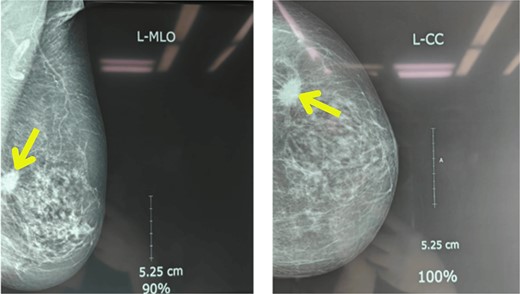

Upon examination, her general condition was fair and vitals were stable. Local examination revealed 3 cm × 3 cm hard, mobile, painless lumps located at 9 o’clock in the right breast 3 cm from Nipple-areolar complex (NAC) and 4 cm × 3.5 cm similar mass at 3 o’clock in the left breast. The axillary and supraclavicular lymph nodes were not palpable. There was no skin, nipple, or areolar changes. Rest of the systemic examinations were normal. Blood and urine tests were within normal limits. Diagnostic mammography revealed well-defined high-density mass lesions of 3.5 × 3.5 cm with spiculated margins in the upper outer quadrants of both breasts and features suggestive of breast imaging reporting and data system (BIRADS) category 5 (Figs 1 and 2).

Mammography showing well-defined high-density mass lesions of 3.5 × 3.5 cm with spiculated margins in the upper outer quadrants of left breast.